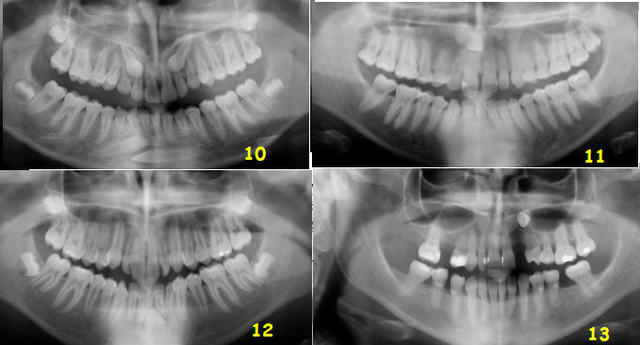

Mmmm Ecrivait:

-------------------------------------------------------

> 10: vestibulaires... toutes !!!

> 11: couronne en mésio-vestibulaire et apex en

> disto-lingual..

> 12: linguale.

> 13: couronne en V et apex en L.

Tout le monde est d’accord ?

Voici la n°10, il ne reste plus qu'une petite erreur... où se cache-t-elle ?

C'était la n°12 qui en réalité était vestibulaire.

Il semble d'ailleurs qu'à la mandibule, les canines incluses le soient toujours..